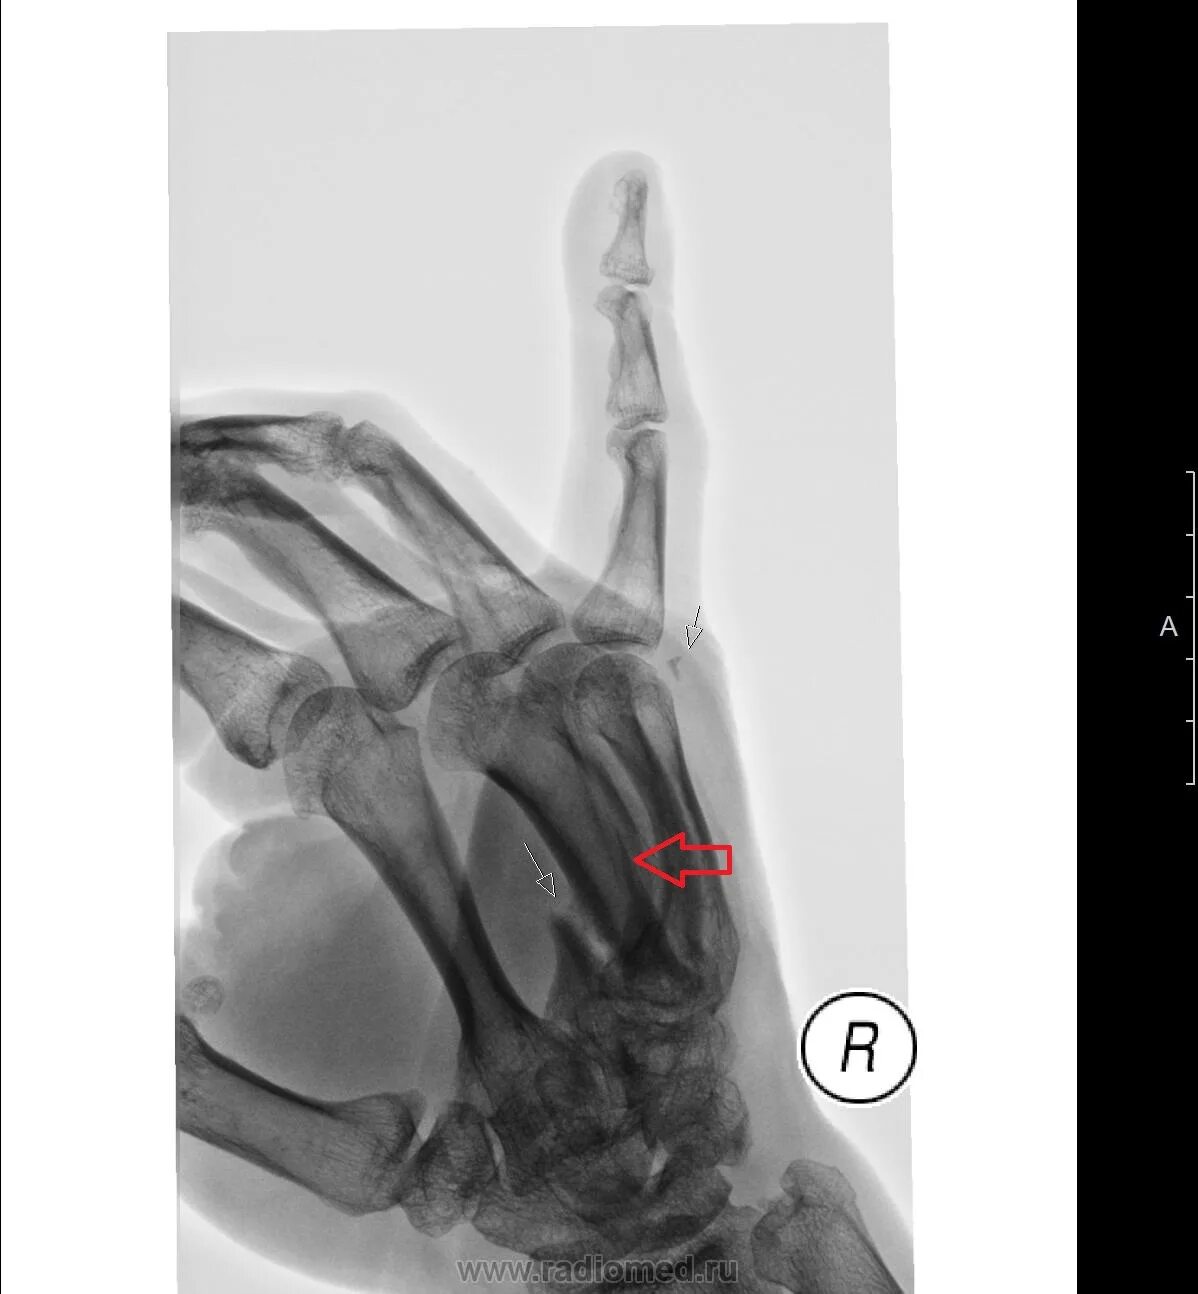

Перелом пястной кости код мкб 10